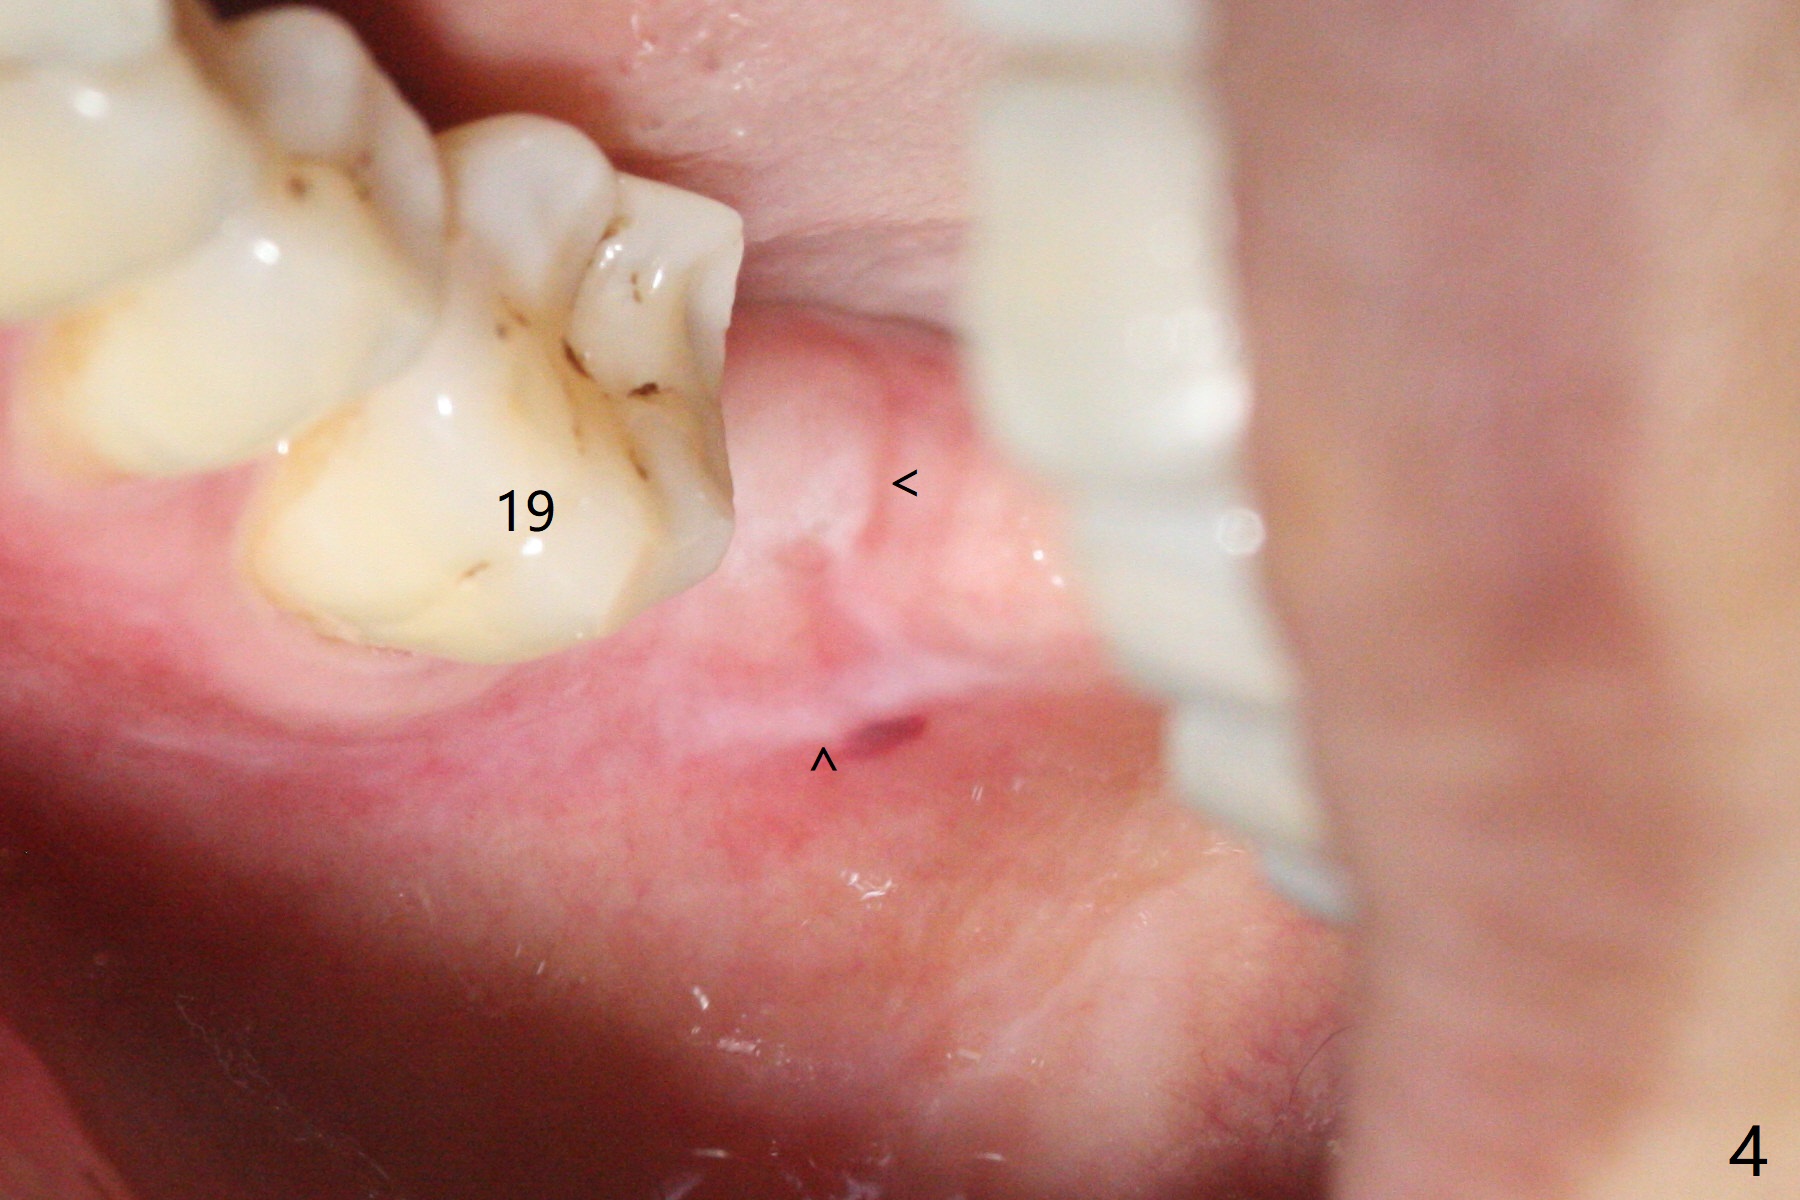

31号牙拔除前近中颊侧有一个瘘道(图一:<),说明32号牙被感染可能性小。术中发现虽然一小部分智齿牙冠与第二磨牙巨大牙槽窝相通(图二:*),但是病变并没有往智齿周围发展(S(可能是牙囊));借助导板(9毫米offset)毫无困难完成钻洞,但是嫌钻洞深度不够。由于植体扭力低(<10 Ncm),只好放置粘性骨粉(图三),覆盖PRF和Cytoplast,PTFE缝线,以及树脂敷料。病人左下第二磨牙缺失多年,牙槽嵴粘膜出现白色病变(图四:箭头),可能与对合磨牙延申有关(图五:箭头)。如果这个牙位需要导板植牙,垂直距离将是一个严峻问题。即种导板(图六:31)与延期导板(18)金属圈放置有不同,相差1.5毫米(图七):即种(由于拔牙)金属圈可以放低,而愈合牙位(由于牙龈存在)金属圈必须放高。所以第二磨牙即种有足够垂直空间优势。术后一周复诊,老的树脂敷料不牢(因为下面没有基台),脱落,下面不可吸收膜没有外翻,重新制作敷料(图八:A)。术后一个月由于2,3号牙之间牙周炎发作,树脂敷料牢靠,下面不可吸收膜稍微暴露,两者取出后,植体略微暴露。没有基台,骨粉固定好像不佳。